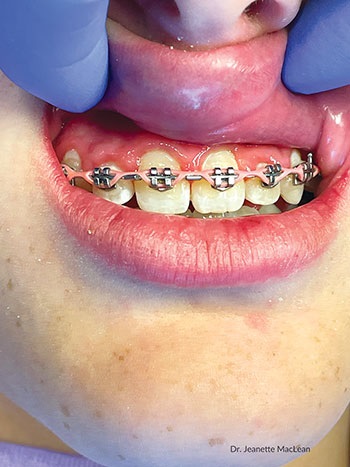

Patient 3: Around orthodontic brackets

Curadont Cases

Fig. 8: A 12-year-old girl in braces with white spot lesions above the brackets on her maxillary incisors. Curodont was applied to help prevent the lesions from getting worse because she would still be in braces for more than a year.

Fig. 9: A 12-month follow-up shows the teeth have not cavitated and some of the enamel translucency has returned.